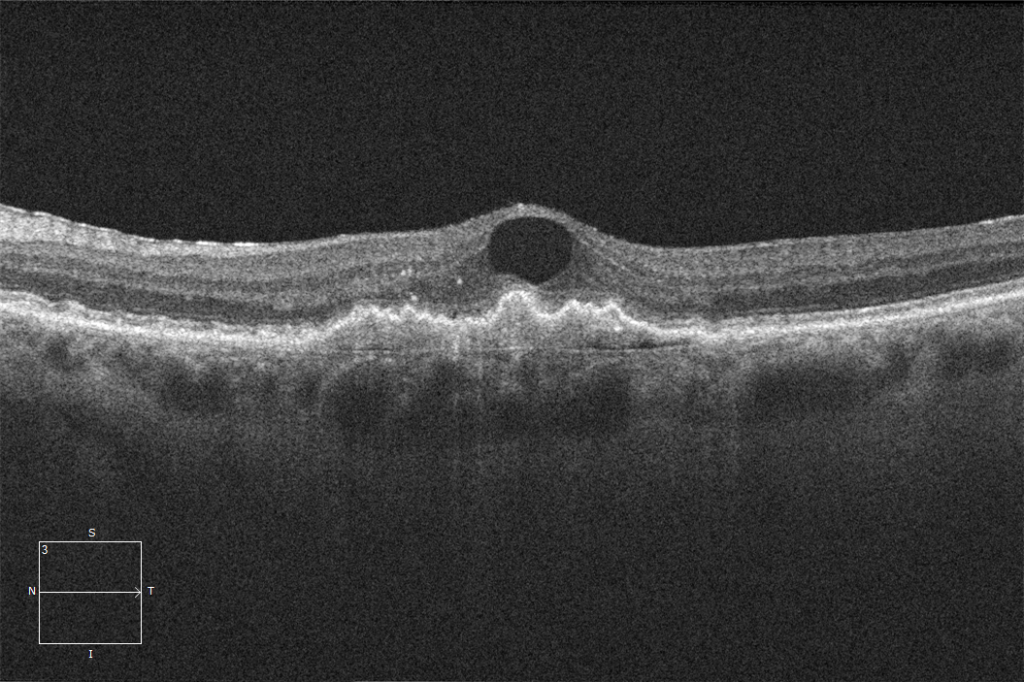

Cystoid Fluid Is it macular degeneration or a venous occlusion? EyeCarePD Macular Degeneration Injections It could help patients maintain vision. Two new drugs that target the complement cascade and stop it from attacking the retina have recently been approved by the. The injections aim to stop the blood vessels from growing and leaking, and to preserve central vision. It usually first affects people in. This treatment is highly effective for. Stops vision getting worse. Macular Degeneration Injections.